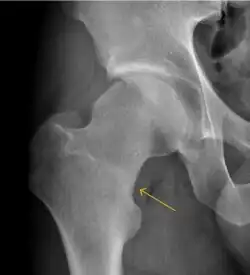

Plain radiography allows us to categorize the hip as normal or dysplastic or with impingement signs (pincer, cam, or a combination of both). Besides these, pathologic processes like osteoarthritis, inflammatory diseases, infection, or tumors can also be identified (Figure 1).[1]

X-ray in pincer impingement type of hip dysplasia

X-ray of cam